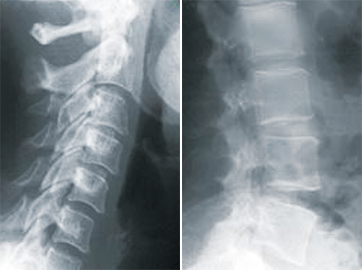

image

正常

• 正常なカーブ

• 正常な軟部組織

• 可動域制限なし

• 正常な神経組織